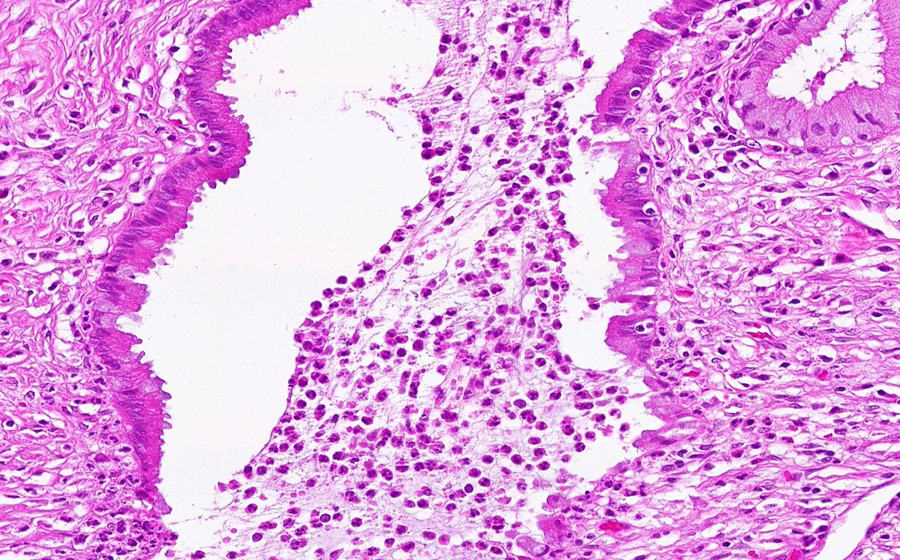

Slide 3: Chronic cervicitis and metaplasia

Histologic section of cervix from a patient with chronic cervicitis (click here to review normal tissue)

Image 4 - 200X

Slide 3 - Image 4